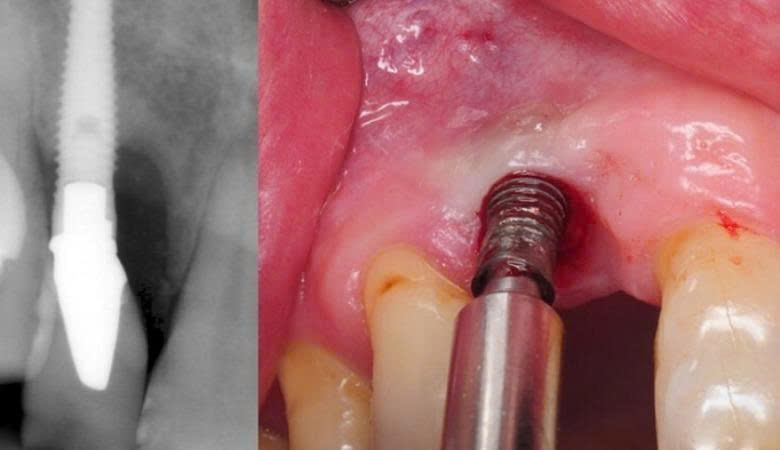

5. Kích ứng và viêm do vật liệu implant kém

Trụ implant pha tạp kim loại như niken, chì hoặc kẽm có thể gây dị ứng, kích ứng nướu, sưng tấy, đau rát kéo dài. Thậm chí, một số trường hợp bị đào thải implant vì cơ thể phản ứng mạnh mẽ.